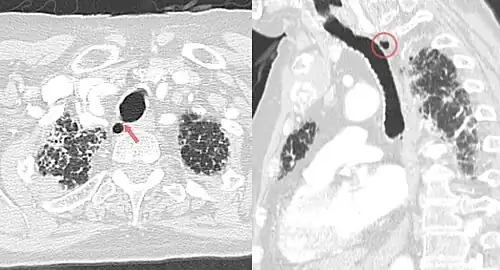

Während angeborene Trachealdivertikel alle anatomischen Schichten der Trachea enthalten, wölbt sich bei erworbenen Formen (Tracheozelen) nur das respiratorische Epithel durch die anderen Schichten nach außen ins Mediastinum vor.[3] Die Divertikel haben meist eine Größe von ca. 0,2 bis 3 cm und die Verbindung zum Lumen der Luftröhre ist oftmals so schmal, dass sie in der Computertomographie und bei der Bronchoskopie nicht gesehen wird.[2][3][13][14]

Trachealdivertikel finden sich in der ganz überwiegenden Anzahl (97 bis 98 %) rechts seitlich hinter der Luftröhre auf Höhe der oberen Thoraxapertur.[2][13][15] Eine zweite, seltene Lokalisation ist die Region der Carina tracheae, wobei diese Fälle schon den Übergang zu den Hauptbronchien betreffen und man daher über die Bezeichnung Trachealdivertikel oder Bronchialdivertikel diskutieren kann.[3]